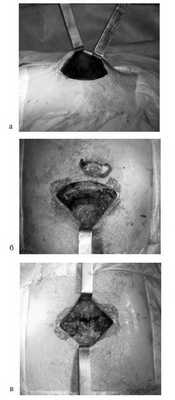

Из 85 операций, выполненных 50 нашим пациентам, 61 произведена из минидоступа с применением видеоторакоскопии. При этом для прошивания легочной ткани использовался сшиватель органов для малоинвазивной хирургии, разработанный проф. Д.Б. Гиллером совместно с фирмой "Уникон" (Россия). Примером подобной операции может служить наблюдение повторной резекции после ранее произведенной нижней лобэктомии слева (рис. 1-4 ).

Техника операции во 2-й группе. С 2002 г. по настоящее время разработан оптимальный метод торакопластики, основными этапами которой являются:

- выполнение на грудной стенке поперечного разреза кожи длиной не более 8 см (рис. 1, г);

- мобилизация кожи, подкожной клетчатки и грудных мышц единым лоскутом (рис. 3, а); Рисунок 3. Интраоперационные фотографии при торакопластике. а - единый кожно-мышечный лоскут; б - резекция грудины; в - сшивание грудины конец в конец.

- поднахрящничная резекция деформированных реберных хрящей (II-VIII ребра) с двух сторон;

- резекция тела грудины до 2-2,5 см в месте наибольшей деформации и сшивание ее конец в конец отдельными узловыми швами (рис. 3, б, в и 4); Рисунок 4. Схема торакопластики при КДГК (2002-2009 гг.).

- послойное ушивание раны с наложением косметического кожного шва.